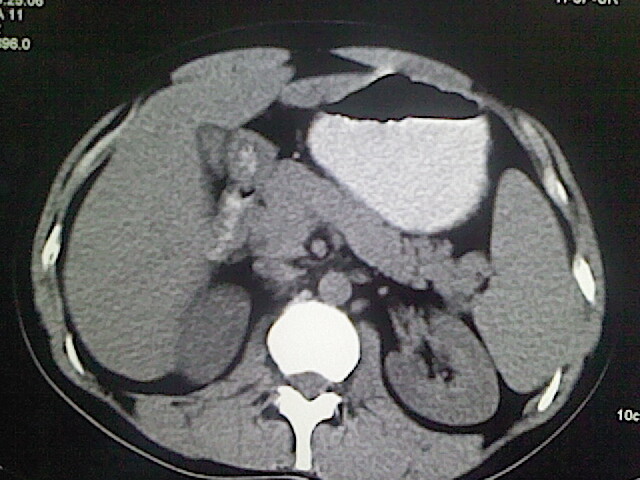

以下是引用卜一在2009-3-14 9:49:00的发言:[br]胆囊萎缩,胆囊壁不规则增厚,内部结构模糊,增强明显强化。另:肝左叶外侧段肝囊肿。支持:慢性胆囊炎!高度可疑:胆囊癌!

以下是引用余辉在2009-3-14 8:48:00的发言:[br]1)慢性胆囊炎。2)肝左叶外侧段肝囊肿。3)脂肪肝。[br]支持,胆囊萎缩,密度增高,不知b超具体有何提示,钙胆汁?结石?

以下是引用jiangjing在2009-3-14 10:18:00的发言:[br]1)慢性胆囊炎。2)肝左叶外侧段肝囊肿。3)脂肪肝。4.】建议行肝功能检查